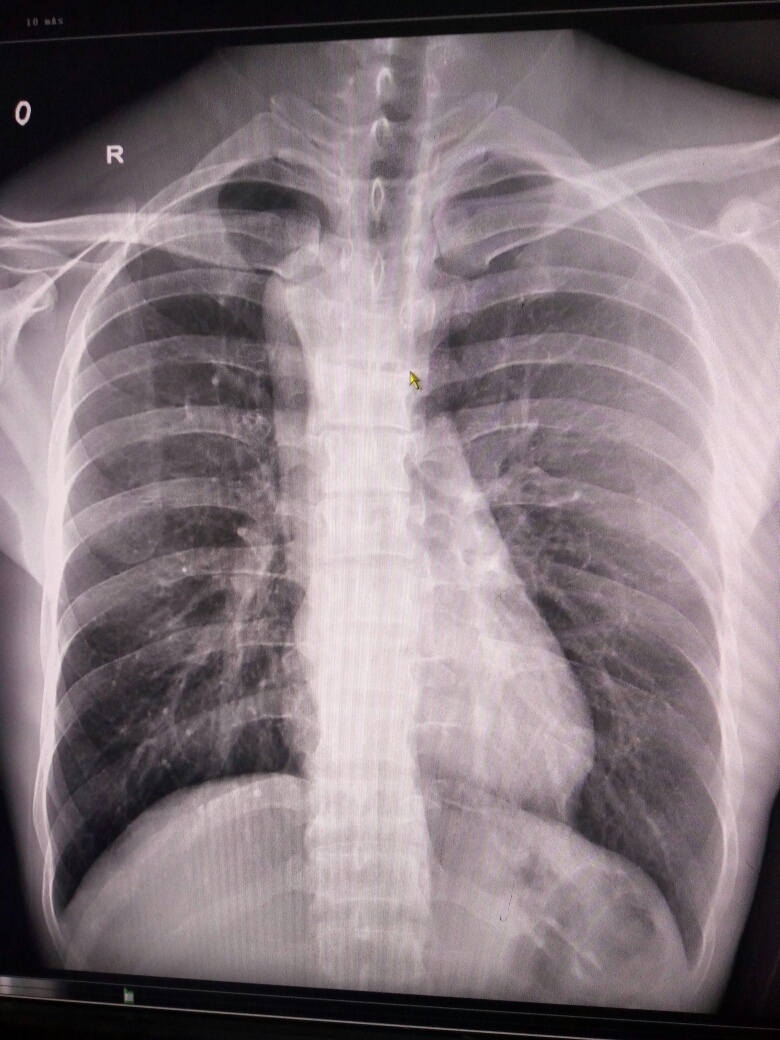

X14085:胸部

主动脉球那去了?请高手点播

右弓右降。

主动脉弓位于脊柱右侧。考虑:右位主动脉弓。

右位主动脉弓,属先天畸形 /

右位主动脉弓。不少见